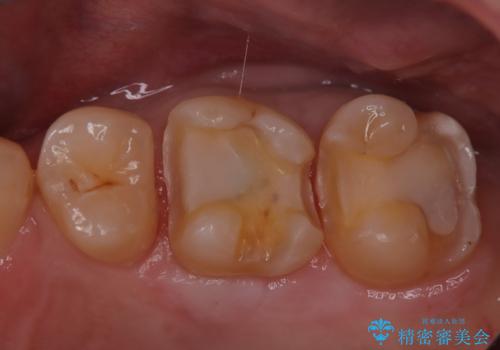

- 定期検診にて虫歯を認めた患者さんです。

患者さんの希望により、修復物の割れる心配が少ないゴールドインレーでの治療を行いました。